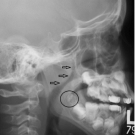

Namita Bhardwaj, MD, MS, MPH; Grant S. Pierre, MD

A 72-year-old woman presented with new-onset right hip pain. Approximately 2 weeks prior, she had fallen on her right hip while walking her dogs.